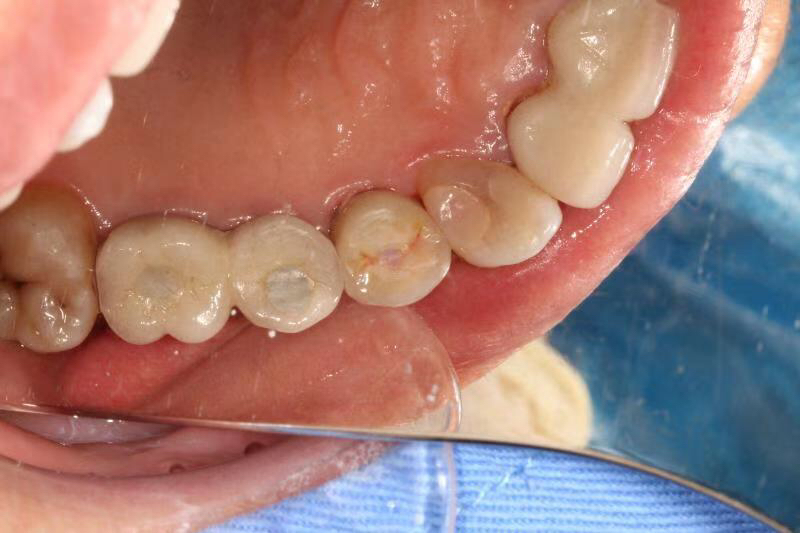

患者女,右上4号牙根管治疗后桩核冠修复,因进食硬物导致桩核冠脱落,未及时处理,导致残根无法修复,从CT上看,牙槽骨高度尚可,所以选择了即拔即种的治疗方案,且术中植骨盖膜、上愈合基台,为患者节省了就诊次数,提前了戴牙时间。